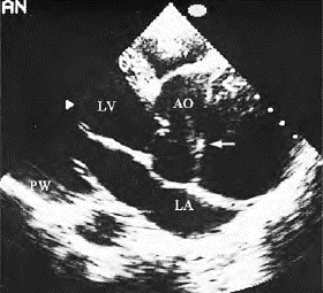

(2)升主动脉夹层动脉瘤:主动脉根部扩大,主动脉壁回声带分离,内层为纤细的低回声,外层回声较强,其间为无回声区,沿主动脉纵轴方向追踪可以发现夹层的起止部位及剥离形态。内膜撕裂则可在管腔内显示纤细的低回声带(图16-16),游离端随血流飘动。

图16-16 马方综合征(主动脉夹层动脉瘤)二维超声图

主动脉根部长轴切面,示主动脉显著扩大,腔内线状回声为断裂的内膜